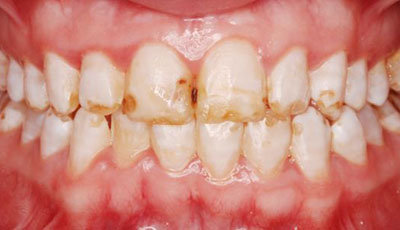

Фото эрозивной, эндемической, штриховой формы

Фото 3. Штриховая форма флюороза, эмаль слегка пятнистая, с несильно выраженными бороздками.